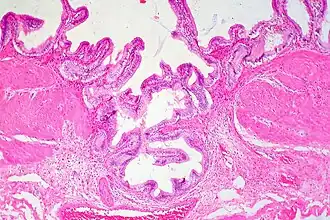

Gallbladder adenomyomatosis is a benign disease of the gallbladder characterized by hyperplasia of the mucosal epithelium and smooth muscle cells inside the muscularis propria.[4][5][6] The excessive proliferation of epithelial cells causes the mucosa to invaginate into the muscular layer lining the gallbladder wall, resulting in characteristic diverticula known as Rokitansky-Aschoff sinuses. These sinuses may be filled with biliary sludge, cholesterol crystals, or gallstones.[4][5][6]

There are three morphologic variants described in the literature – diffuse, segmental, and localized.[5][6] Diffuse, also known as generalized, adenomyomatosis has a widespread distribution of hyperplastic changes and thickening across the gallbladder wall.[5][6] The localized form of adenomyomatosis is also known as a gallbladder adenomyoma (in a similar manner that uterine adenomyoma is the localized variant of adenomyosis). The localized form is a single mass, typically in the fundus, that protrudes into the lumen of the gallbladder in the form of a polyp.[5][6] The segmental form is characterized by its annular (ring-shaped) distribution of adenomyomatosis in the body of the gallbladder, often giving it an hourglass-like appearance.[5][6]